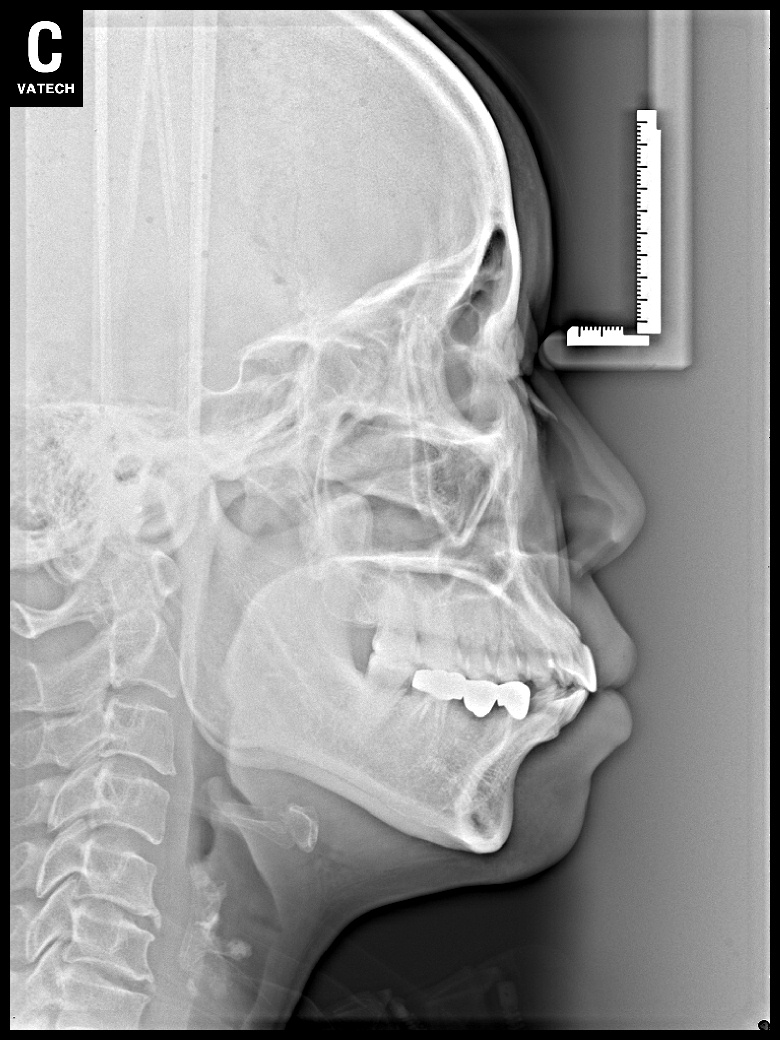

치료 후 사진입니다.